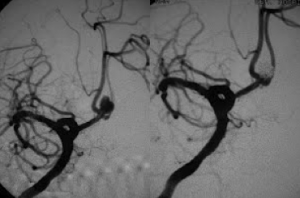

Στις παρακάτω εικόνες απεικονίζονται τα αποτελέσματα Εμβολισμού πραγματικών ανευρυσμάτων εγκεφάλου:

![]() |

| Ανεύρυσμα πρόσθιας αναστομωτικής αρτηρίας πριν και μετά τον εμβολισμό |